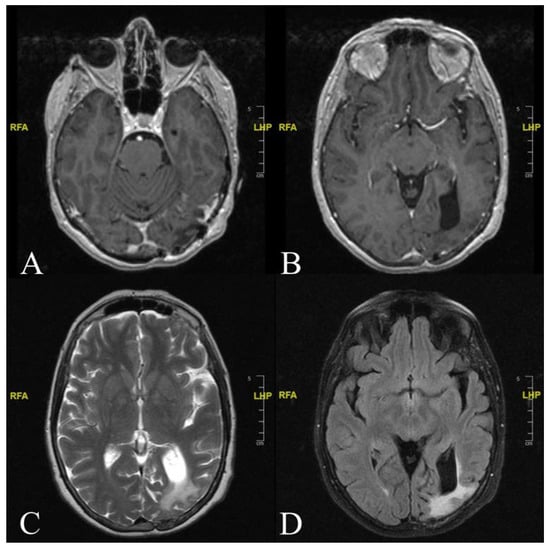

2. Case Report